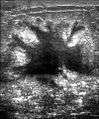

Ultrasound image shows irregular shaped mass of breast cancer.